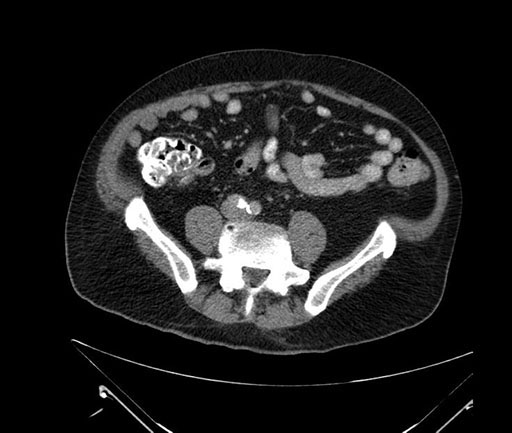

Axial - stented